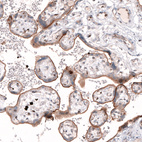

Immunohistochemical staining of human placenta shows strong membranous positivity in trophoblastic cells.